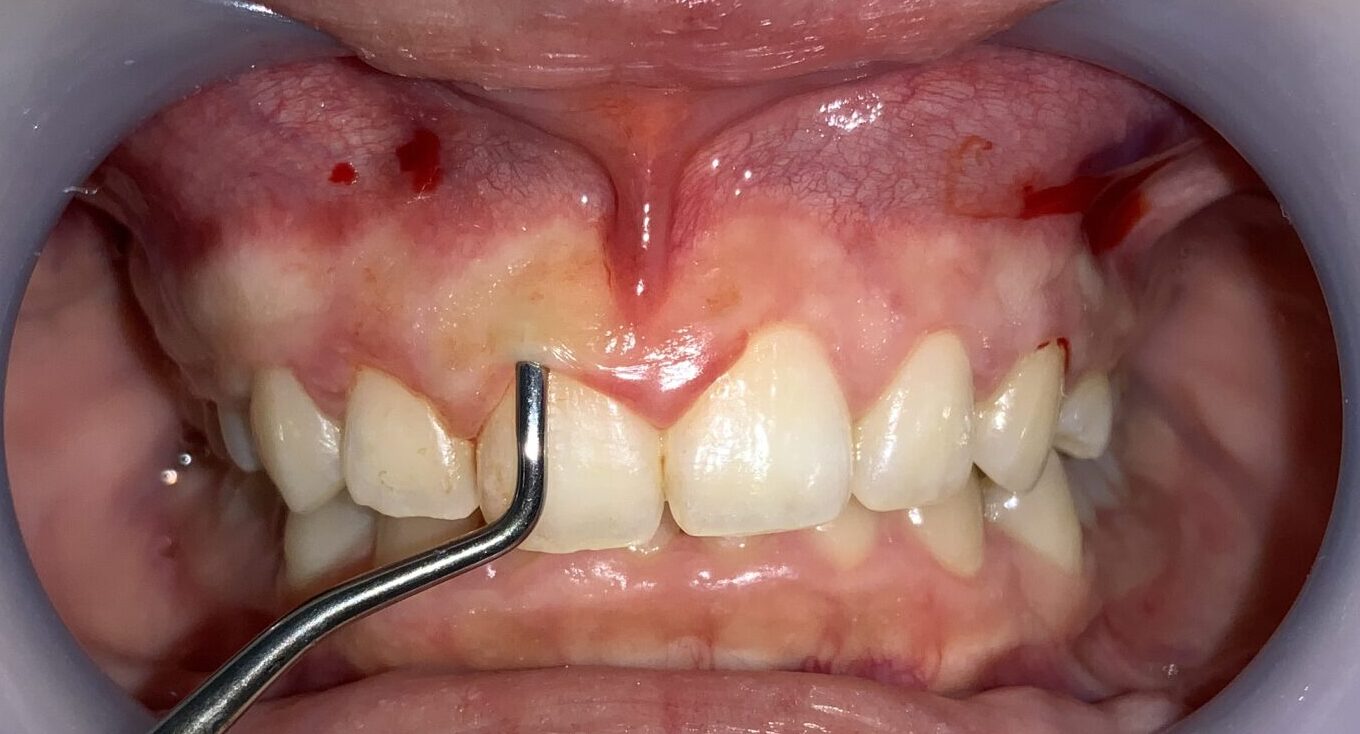

前歯から順番に検査をして参ります。

歯ぐきの被っている量は相当あります。また、歯ぐきが分厚くて、繊維状に変性をしているようです。しっかり整えましょう。

前歯の隣の歯です。

こちらの歯の歯ぐきも分厚くかぶさっているようです。

安全に切り取ることができる範囲がわかります。

血液が出ているのは、局部麻酔の影響です。歯の検査の影響ではありませんので、ご心配なく、検査をお受けください。